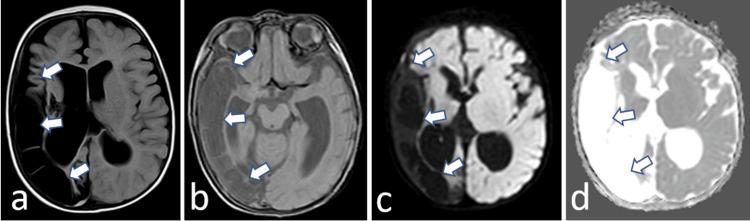

婴儿烟雾病罕见病例:中风后神经康复的复杂性

A Rare Case of Moyamoya Disease in Infancy: Complexities in Post-stroke Neurorehabilitation.

Although ischemic stroke in infants is not very common, it remains one of the causes of morbidity and mortality in children. One of the etiologies is Moyamoya disease, which remains a rare entity in Morocco. Management of this disease in the pediatric population remains precarious due to delayed diagnosis, given the diversity of clinical presentations and the lack of necessary technical means, such as MRI or angiography, allowing early diagnosis, as well as the lack of standardized international rehabilitation protocols and the absence of pediatric rehabilitation structures in underdeveloped countries. Through this case report of a four-month-old infant who suffered an ischemic stroke in a Moyamoya, we discuss the diagnostic difficulties and its rehabilitation challenges.

摘要

虽然婴儿缺血性中风并不常见,但它仍是儿童发病和死亡的原因之一。病因之一是烟雾病,在摩洛哥它仍然是一种罕见的疾病。由于临床表现多样且缺乏必要的技术手段(如MRI或血管造影)以进行早期诊断,以及缺乏标准化的国际康复方案且欠发达国家没有儿科康复机构,导致诊断延迟,儿科人群中这种疾病的管理仍然不稳定。通过这份关于一名4个月大患烟雾病缺血性中风婴儿的病例报告,我们讨论了诊断困难及其康复挑战。